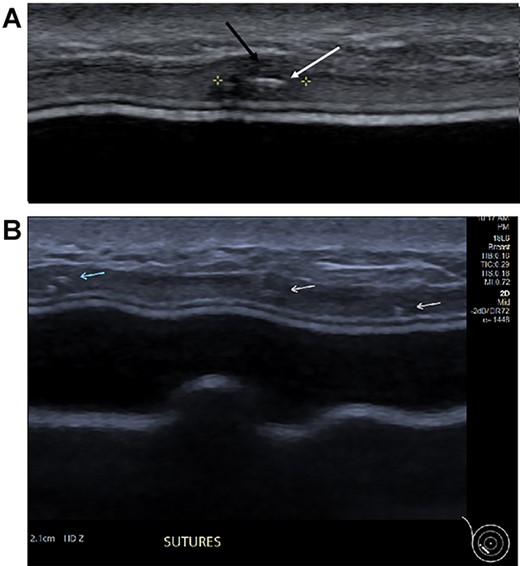

Clinical findings during follow-up were unremarkable until 2020, when she represented with a new lump in the reconstructed left breast neighbouring the mastectomy scar inferiorly. A 1 cm subcutaneous lump with no skin tethering, was palpable along the uniting suture line of the ADM-pectoral muscle. Imaging with ultrasound was indeterminate. This implant proximity rendered it unsuitable for core biopsy due to the high risk of iatrogenic implant perforation (Fig. 2). Subsequent MRI (Fig. 3) illustrated an 11 mm low signal lesion correlating clinically to the palpable lump with mild enhancement but indeterminate appearance.

Axial post contrast fat-saturated sequence identified bilateral implants and an 11 mm oval foci of type 1 enhancement in the site of clinical concern on the capsule (black arrow).